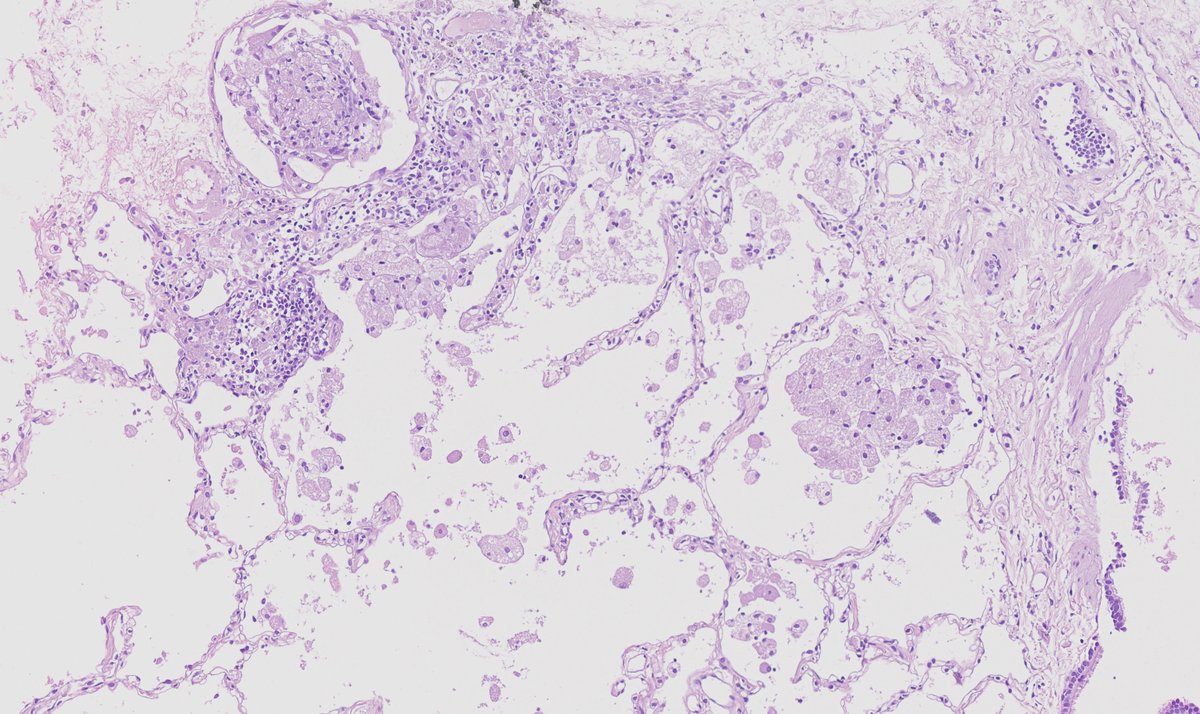

F40y,chronic cavitary pulmonary aspergillosis, atypical resection of the low lobe of the lung.

several cavities with a fungal ball, granulation tissue, chronic inflamation, metaplastic squamous epithelium, calcium oxalate crystals